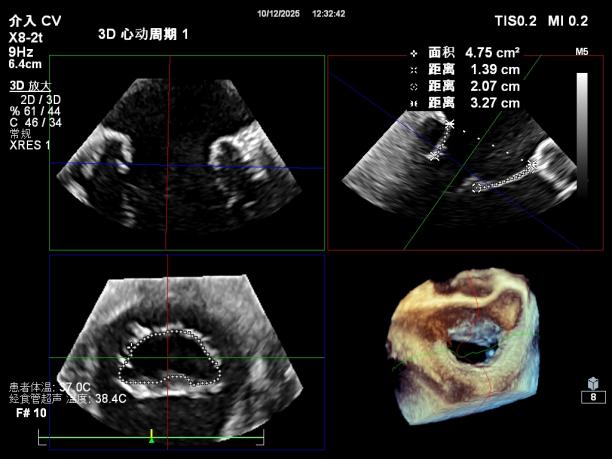

【瓣膜与功能特点】

前超声评估明确关键指标:二尖瓣瓣环呈扩张状态(前后径约3.3cm,瓣环面积约4.75cm²,前叶长约2.1 cm,后叶长约1.4 cm),瓣叶增厚且后叶栓系明显,前后叶对合不良;同时伴左房、左室明显扩大,左室收缩功能显著减低,合并节段性运动异常。经团队综合评估,该患者为“多支冠脉支架植入后+低射血分数+重度功能性二尖瓣反流(混合性MR)”的高危病例,左室射血分数(EF)仅20%,在接受GDMT药物优化治疗6周后EF值提升至27%,但症状仍无法有效缓解,遂决定为其实施经心尖入路二尖瓣缘对缘修复术(TA-TEER)。